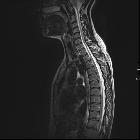

Spinal astrocytomas usually span multiple segments in craniocaudal extent, with an average length of involvement of 4-7 vertebral body segments .

Regarding their specific spinal location:

- involvement of thoracic cord (67%), followed by cervical cord (49%), are most common. Tumor may, of course, involve both regions

- involvement of entire spinal cord (holocord presentation) - more common in children than in adults

Astrocytomas are typically intramedullary masses that diffusely expand the spinal cord. They usually span spinal multiple segments, as discussed above. Their slow outward growth tends to cause osseous remodeling of the spinal canal, which may be the only clue to their presence on x-ray or CT.

As astrocytomas arise from cord parenchyma (c.f. ependymomas that arise in the central canal), they typically have an eccentric location within the spinal cord.

They may be exophytic and even appear largely extramedullary. They usually have poorly defined margins. Peritumoral edema is present in ~40%. Intratumoral cysts are present in ~20% and peritumoral cysts are present in ~15%. Unlike ependymomas, hemorrhage is uncommon.